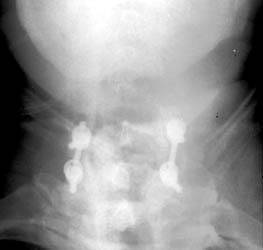

65 y.o male with prior surgery 23 years ago, secondary to trauma involving

C4-5, C5-6 ACDF procedures. Now is 1 yr s/p bilateral C5 and C6 foraminotomy and

C6-C7 posterior fusion and right iliac crest bone graft for persistent numbness

and tingling for 2 years.

Radiographs obtained 5 months post-operatively demonstrate normal

C6-7 fusion without evidence of hardware failure. |